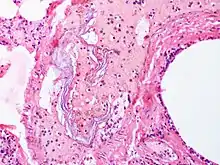

| Intravascular squames are present in this example of amniotic fluid embolism. | |